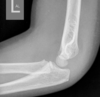

Cisto ósseo simples com fratura

Lesão litica unicameral.

Localização: úmero proximal e femur (< 20 anos) ou calcâneo, talus, ileo (> 20 anos).

Se fratura: Sinal do fragmento caído.